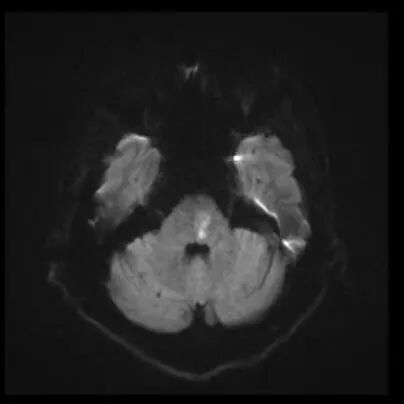

近日,江苏省人民医院(南京医科大学第一附属医院 江苏省妇幼保健院)神经内科接诊了一位经历两次中风的年轻患者。28岁的于先生(化名)热爱运动、自认身体健康,两个月前,在一次打完篮球后,突发右侧肢体无力、不能言语。经检查,医生发现其左侧椎动脉V3段夹层动脉瘤,基底动脉闭塞,随即进行基底动脉闭塞机械取栓术。术后血管恢复通畅,功能基本康复。

然而,术后仅一个月,出于对自身健康的自信,于先生再次走上篮球场。不幸的是,这次剧烈运动后脑干出现新发梗死,虽经积极救治,仍遗留右侧肢体偏瘫、言语不清等严重后遗症。

急性脑干梗死